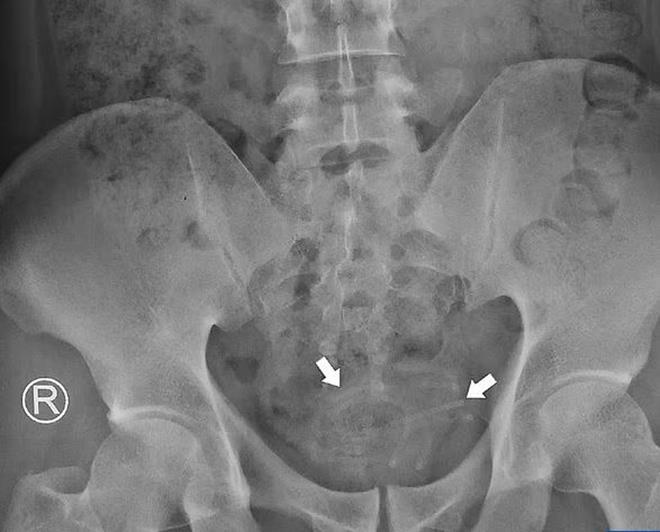

Dây tai nghe mắc kẹt trong bàng quang của người đàn ông.

Trong bài báo khoa học đăng trên tạp chí Radiology Case Reports, bác sĩ điều trị ca bệnh này cho biết, ban đầu, ông cho bệnh nhân chụp X-quang để kiểm tra mức độ xâm nhập của dị vật vào cơ thể và sự tổn thương mà nó gây ra. Ông nhanh chóng phát hiện sợi dây tròn đường kính 3mm, nằm cuộn lại trong bàng quang. Rất may là nó không dính vào thành bàng quang.